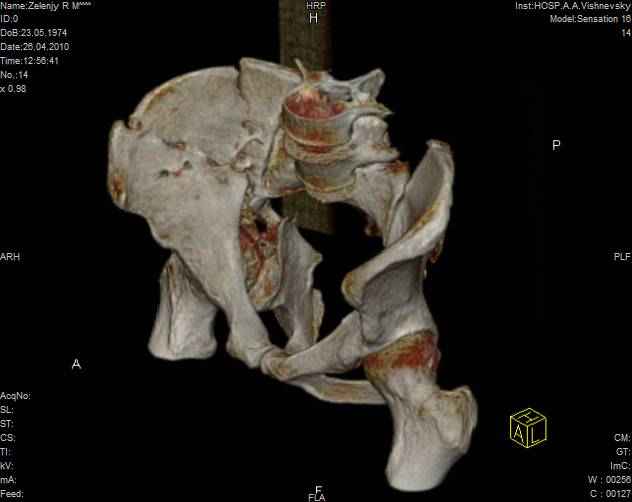

Молодой человек, 35 лет в первых числах января 2010года попал в ДТП, получил перелом правой половины таза.

Был доставлен в одну из ведущих клиник Москвы и прооперирован: была вополнена открытая репозиция и остеосинтез крыла правой подвздошной кости с прилегающей к нему края вертлужной впадины. Но по каким то, мне е понятным соображениям, перелом седалищной кости, проходищая через вертлужную впадину не был отрепонирован ( со слов пациента, доктор сказал что перелом и так срастется).

В настоящее время имеем то что имеем - видно на картинках. Пациент кода то лечился у меня, потому попросил проконсультировать его в создавшейся ситуации.

Мое мнение: пациенту конечно, рано или поздно, предстоит эндопротезирование правого тазобедреного сустава. Но хотелось бы вертлужный компонент поставить в более сформированню вертлужную впадину, чем сейчас имеется.